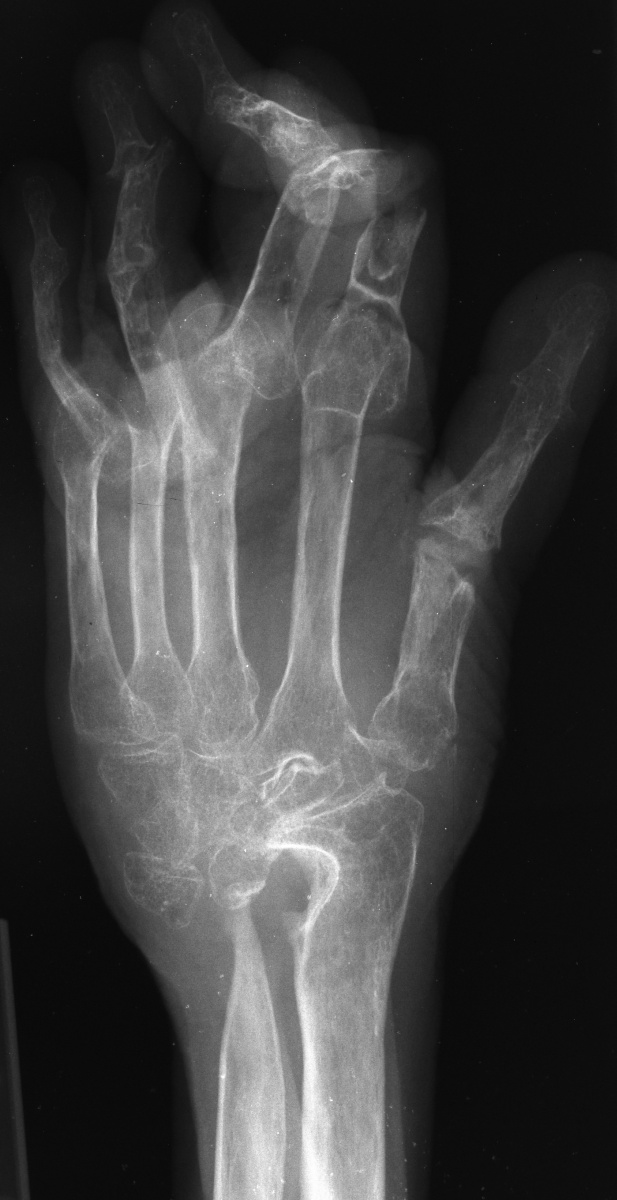

This woman has undergone multiple rheumatoid procedures elsewhere. On the right, these included right wrist fusion and MCP silicone arthroplasties. On the left, silicone arthroplaties of the thumb MCP, index and middle PIP joints and arthrodesis of the thumb IP, ring and small PIP koints. She wanted improvement of her left hand function, which was hindered by wrist pain and flail fingers.

Xrays show radiocarpal collapse, proximal migration of the proximal phalanges, flail PIP joints and loss of the proximal half of the dorsal cortex of the proximal phalanges.

Her greatest desire was pinch reconstruction. This was approached in two stages: wrist fusion, implant removal and fusion of the index and middle PIP joints, followed by index and middle MCP arthroplasties. There are several alternative approaches, including index MCP fusion and revision PIP arthroplasties.